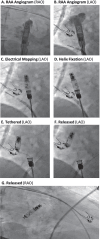

Results: Aveir AR devices were implanted per standard local practice (N = 75 patients; 3 centers; 72 ± 13 years; 52% male; 92% de novo) with 100% success and placed predominantly in the right atrial appendage base (83%). The total procedure duration (from first incision to final suture) was 36 ± 33 min and the cumulative fluoroscopy duration was 7 ± 8 min. Pre-fixation mapping made repositioning unnecessary in 95% of implants. Pacing capture threshold at 0.4 ms pulse width, sensed amplitude, and impedance values of 0.6 ± 0.6 V, 2.9 ± 1.5 mV, and 329 ± 46 Ω, respectively, were measured prior to patient discharge. Capture threshold and sensed amplitude had improved significantly from LP release to patient discharge. No acute complications were observed.

Figures